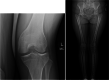

Purpose of review: Discoid lateral meniscus (DLM) is a well-known meniscus variant, and comprises excess and thickened meniscal tissue, altered collagen ultrastructure, and peripheral instability. This article presents a comprehensive review on current knowledge of DLM, focusing on pathology in parallel with surgical techniques and outcomes.

Recent findings: A paradigm shift in surgical management of DLM is taking place as knee surgeons are seeing more patients with long-term sequelae of partial lateral meniscectomy, the standard treatment for DLM for many years. Surgical treatment has evolved alongside the understanding of DLM pathology. A new classification system has been proposed and optimal surgical techniques described in recent years. This article highlights up-to-date evidence and techniques in management of both acute DLM tears and joint restoration following subtotal meniscectomy for DLM. Surgical management of DLM must be tailored to individual pathology, which is variable within the diagnosis of DLM. We present an algorithm for management of DLM and discuss future directions for the understanding and treatment of this debilitating condition.